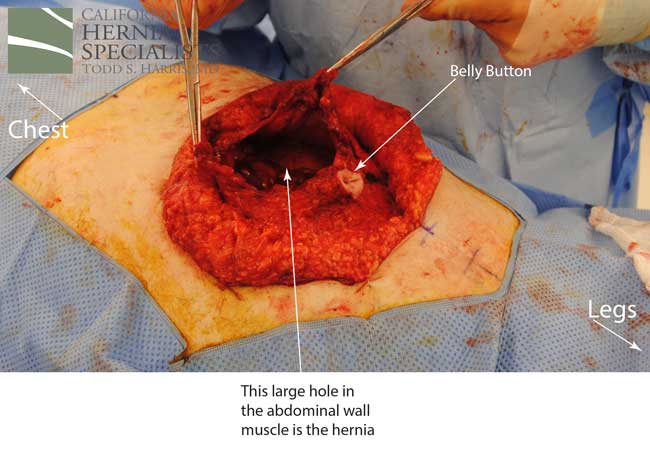

The more complete approach would be to bring healthy muscle together at the mid line. Only after the muscle is repaired completely, can a mesh be used to SUPPORT the muscle repair. Meshes should not be considered a bridge from healthy muscle to healthy muscle. Instead mesh should be used as a reinforcement of a correct hernia repair.

This technique requires more surgical time, recovery time, and usually several days in the hospital. However, this patient chose to proceed with the open hernia repair. Below are some of the pictures from his surgery as well as post operative CT scan image and photos of the patient.